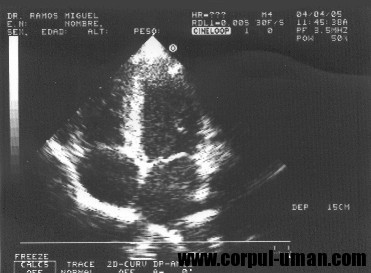

Ecocardiograma este o tehnica de diagnostic lipsita de durere, non-invaziva, care foloseste ultrasunetele.

Ecocardiograma ofera cardiologului o evaluare superba, simpla si lipsita de risc referitoare la valvele cardiace, muschiul cardiac, forta de contractie a muschiului si determinarea fractiei de ejectie.

Marimea fiecarei camere poate fi masurata si, in particular, marirea muschiului cardiac poate fi determinata cu usurinta.

Deoarece contractia miocardului poate fi vizualizata, ecocardiografia este folosita la unii pacienti dupa un infarct miocardic acut, pentru a detecta complicatiile speciale.

Ecocardiograma este cea mai utila pentru pacientii cu pericardita si pentru detectarea acumularilor de apa din jurul inimii (efuziune pericardica). Ca urmare, ecocardiograma este o analiza foarte utila.